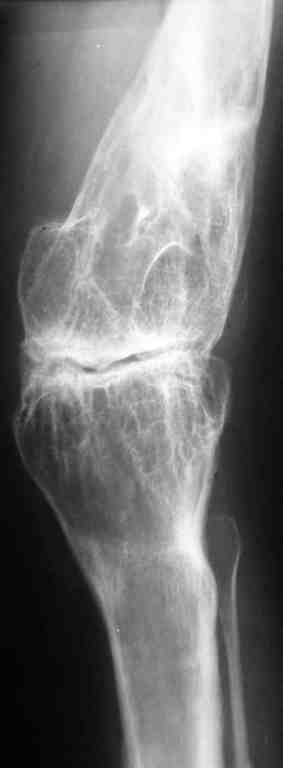

DS: Врождённая аномалия развития левой нижней конечности. Состояние после удлинения бедра и голени (около 45 см). Варусная деформация шейки лев. бедра. Лев. коксартроз II ст. Лев. гонартроз III ст. Разгибательная контрактура лев. коленного сустава. Парез малоберцового нерва слева. Укорочение лев. н/конечности 1,5 см.

St. localis: ходит в брейсе с опорой на 1 трость. Относительная длина ног S – 1,5 см. Движения в лев. т/б суставе: сгиб. 70, разг. 180, привед. 60, отвед. 110, вн. рот. 20, нар. рот. 10; в лев. к/сус. пассивно: сгибание 0, разг. - 180+ 30; активно на переразгибание и из положения переразгибание на сгибание 2балла. Под нагрузкой вальгусно-рекурвационная деформация: клиничски на val. – 15-20, rec. - 30. Движения в лев. голеностопном суставе (акт./пас.): тыл. фл. 0/90, под. фл. 170, отвед. 10/15, прив. 25. Функция в других суставах не нарушена.